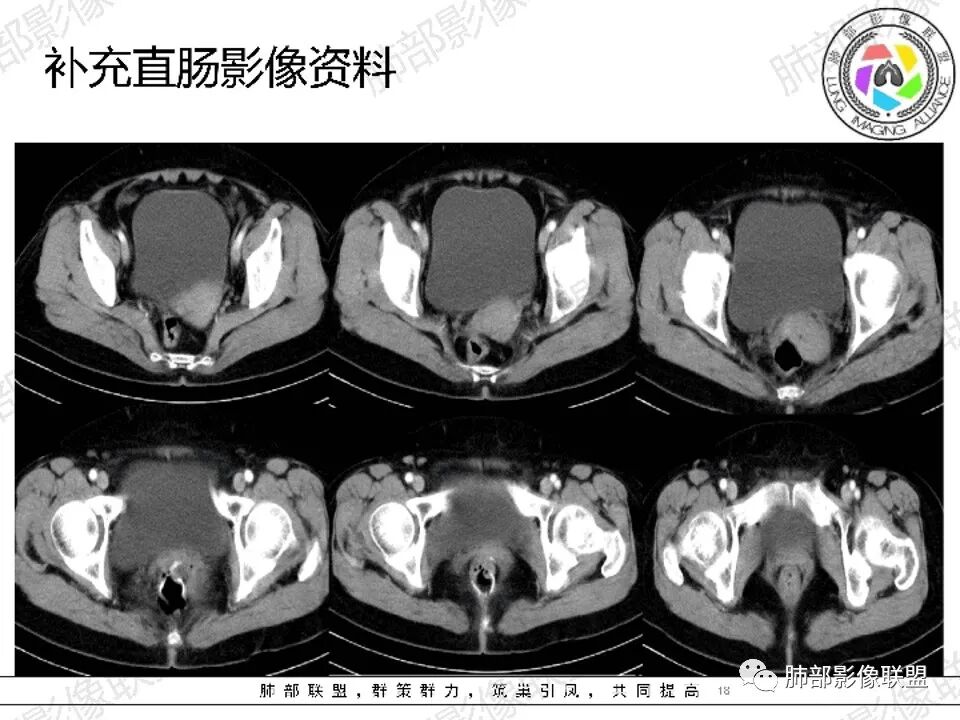

△直肠术区壁增厚,外壁欠清,局部强化偏低,转移瘤确实要考虑

△宫颈局部确实有受压的迹象

△直肠术区局部肠壁增厚了,增强局部有低强化灶,直肠确实符合复发的表现,还是要恶性首选